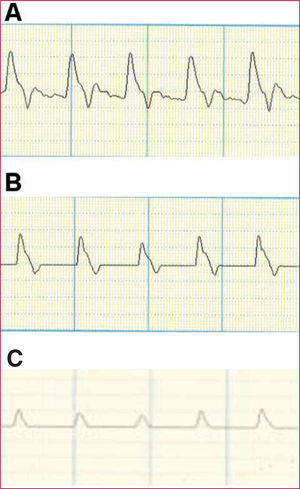

Finally, recording the velocimetric wave obtained by Doppler can also provide very useful information by means of evaluating the changes in the different components of the arterial velocimetric wave (Figure 2).

Figure 2. Doppler velocimetric wave. A: normal study. Prominent systolic wave with dicrotism in the descending wave. B: mildly pathologic study. Absence or reduction of the dicrotism in the descending wave. C: very pathologic study. Flattening of the systolic wave.